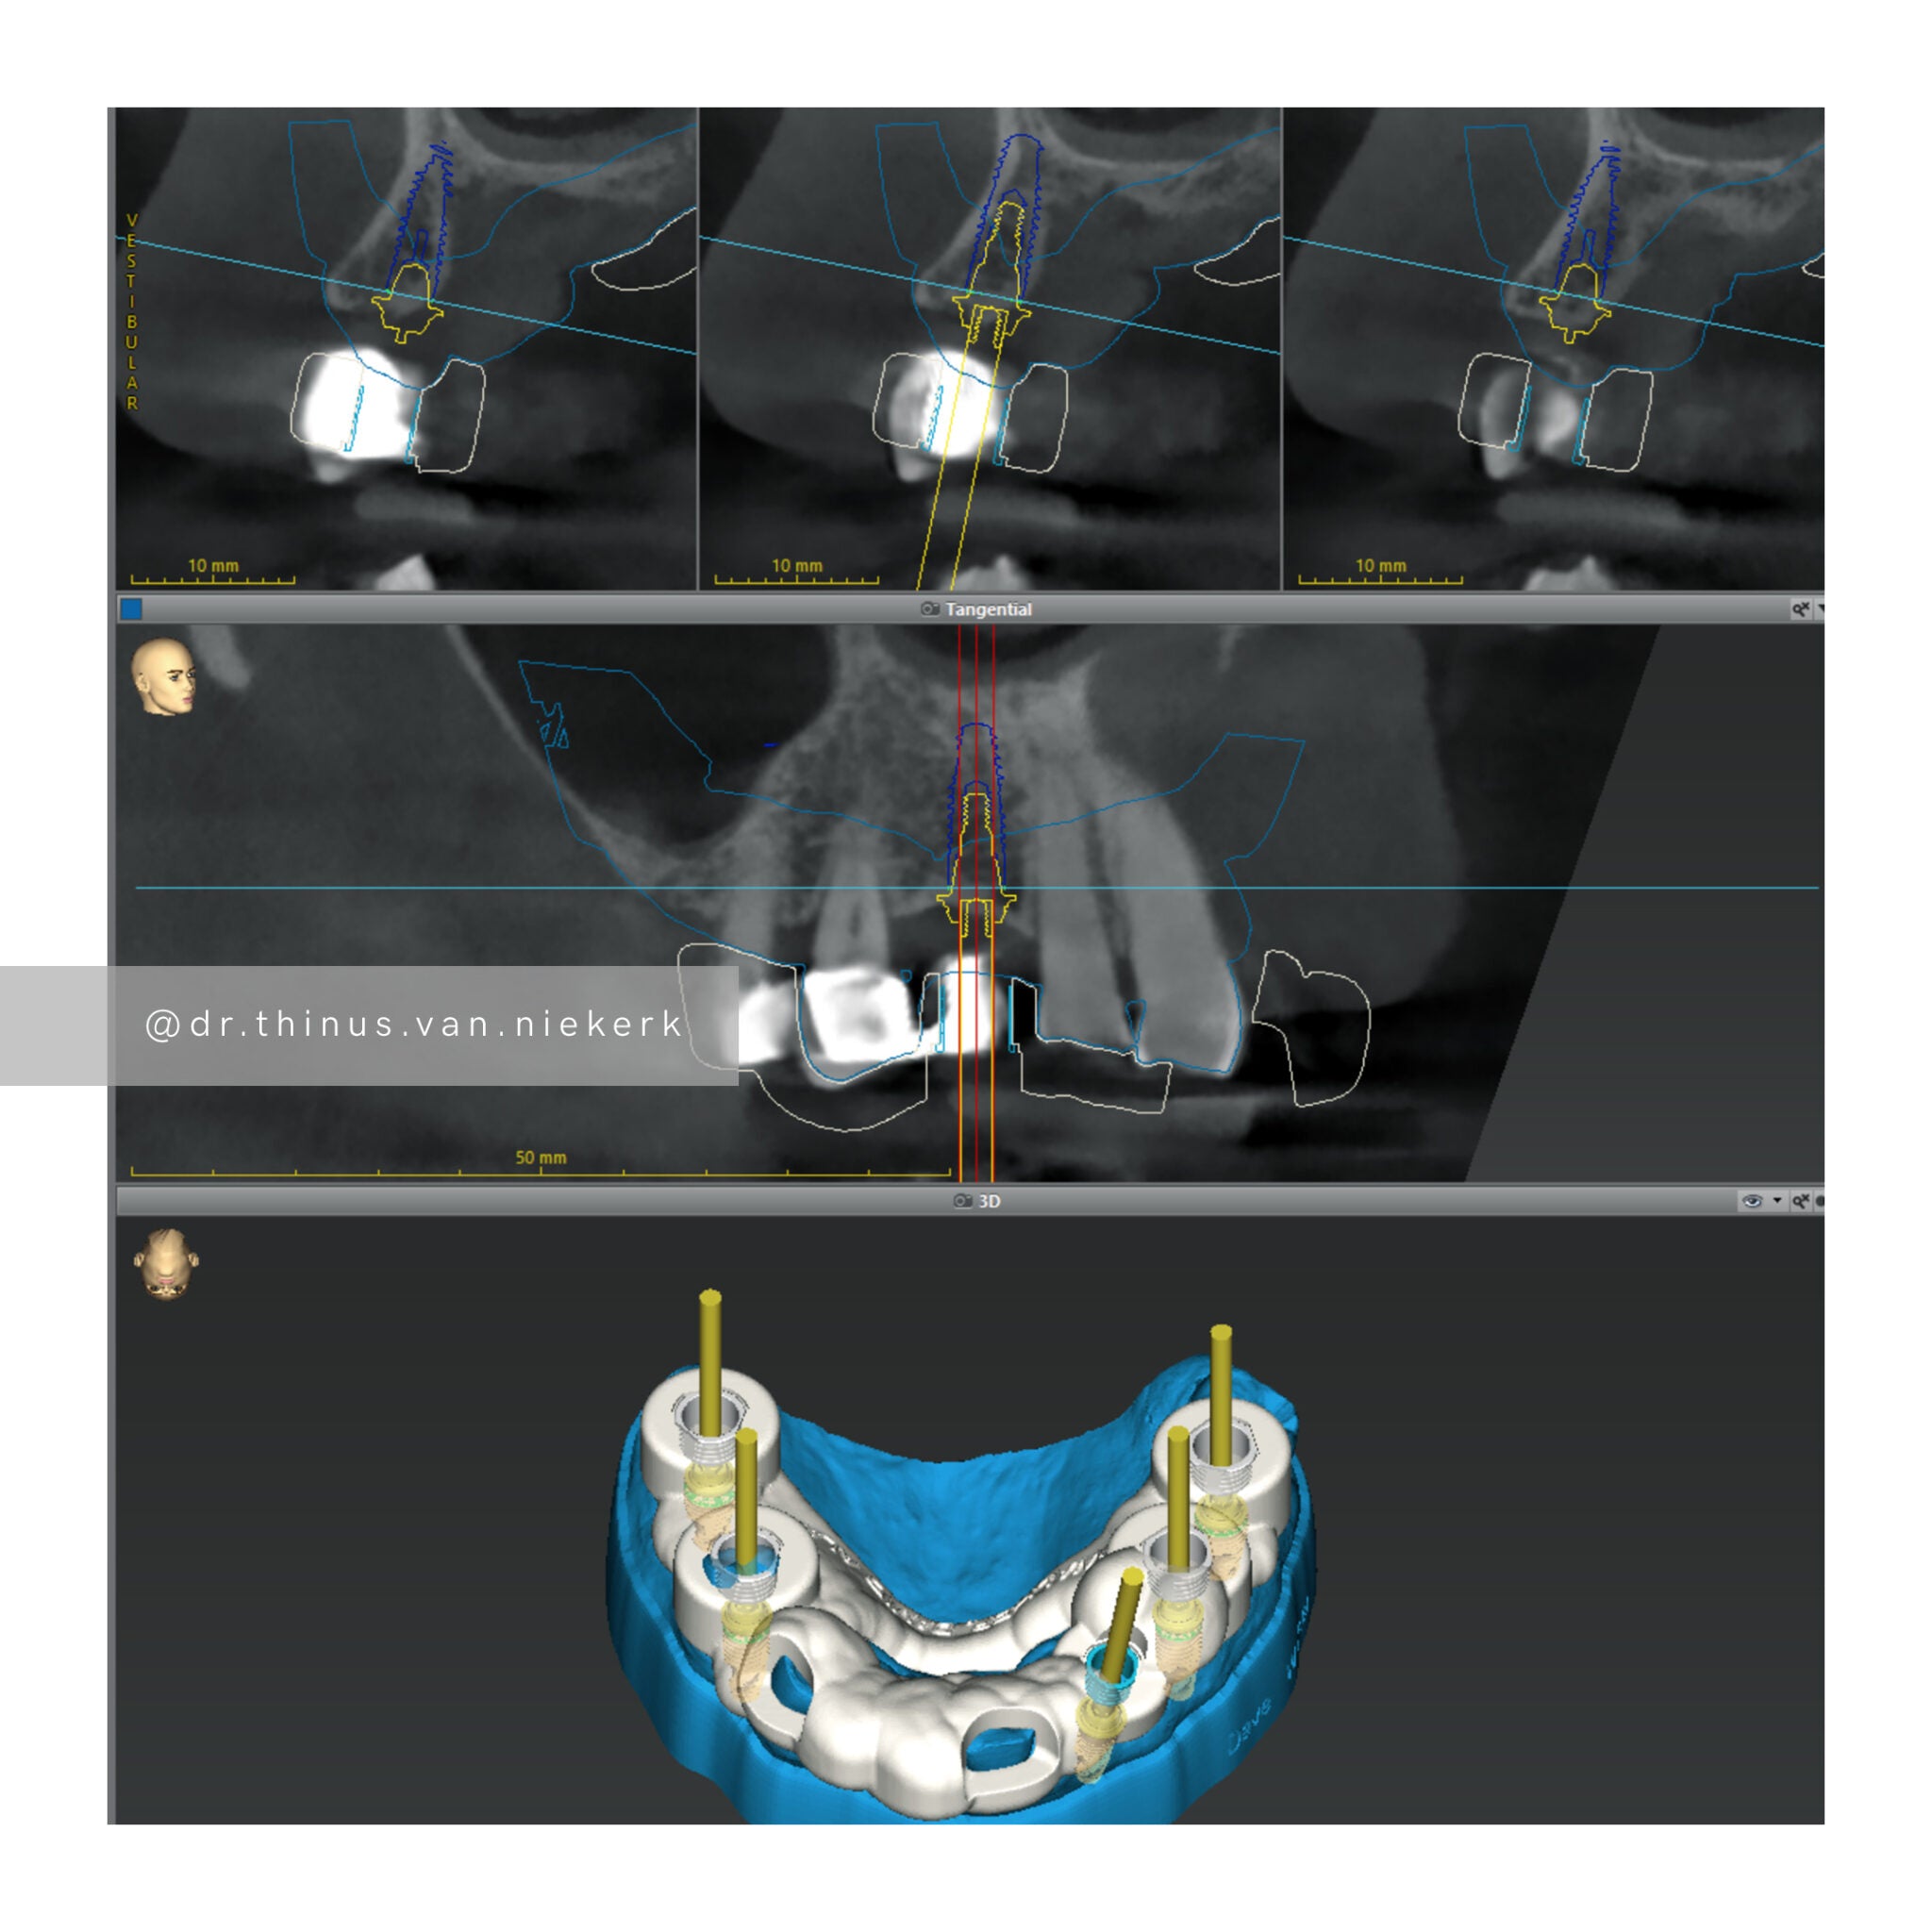

This is the Sirona Axeos 3D CBCT machine. This is also the starting point for every patient and an invaluable tool in the diagnosing and treatment planning processes. The machine is unique in that it produces incredibly sharp, large volume images - perfect for implant and rehabilitation dentistry.

The Trios 4 by 3Shape produces extremely accurate 3D scans of patients’ mouths, replacing traditional impressions. When merged with the 3D volumes created by the CBCT machine, these 3D scans make digital implant and rehabilitation planning possible. They are an excellent visual tool to show the treatment process.

Able to print a host of different biocompatible materials, the 3D printer allows digital scans and designs to be processed in a clean and accurate workflow. Used to print prototypes, models guides and much more, the power of 3D printing in dentistry is unparalleled, offering novel treatment solutions.